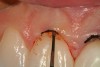

The first step prior to adjusting the heights of the tissue was to measure the depth of the gingival sulci to determine if there was adequate free gingival present to make an adjustment in the tissue levels and maintain a minimum sulcular depth of 1 mm (Figure 3). Again, there must be a minimum of 1 mm of sulcus depth remaining apical to the proposed corrected level; otherwise, a bony correction would be needed as well. The needle electrode (Figure 4) was used at the lowest setting (in this case, 3) which yielded a smooth cut (Figure 5). When the procedure was complete (Figure 6 and Figure 7), the remaining sulcus depth was verified with a periodontal probe and the surgical site was debrided with hydrogen peroxide solution (Figure 8). A 2-week postoperative view (Figure 9) with the patient wearing provisional restorations shows nice healing and gingival zenith levels that are more symmetrical. The restorative margins were placed subgingivally to mask out the darkness of the root structure on tooth No. 9. Figure 10 shows the patient after the definitive restorations were placed.

Figure 3  A periodontal probe verifies the sulcus depth at 3 mm from the gingival crest. The planned gingivectomy procedure would not require bony crown lengthening since a minimum sulcus depth of 1 mm would remain after the procedure is completed.

Figure 3